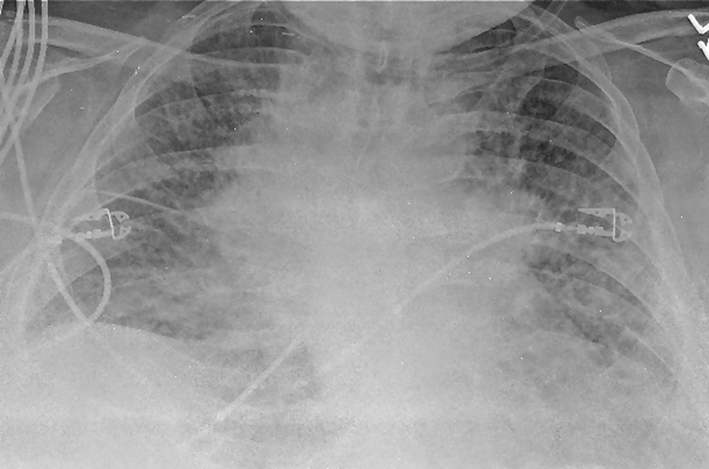

Laboratory studies were significant for anemia with hemoglobin at 11 (12 - 15.5 g/dL) and leukocytosis with WCC 15.41 (3 - 11 × 103 mL). His creatinine was 0.67 (0.3 - 1.2 mg/dL) and B natriuretic peptide level was within normal limit at 53 (0 - 99 pg/mL). Chest X-ray showed bilateral perihilar haziness, consistent with pulmonary edema (Fig. 1). His electrocardiogram revealed sinus tachycardia with right bundle branch block. An echocardiogram demonstrated a good left and right ventricular systolic function (left ventricular ejection fraction 59%), grade-1 diastolic dysfunction with trivial tricuspid regurgitation. A diagnosis of diastolic heart failure was considered and patient was treated with diuretics, aiming daily negative fluid balance of 500 - 1,000 mL. He had lost 2 kg of weight since admission within a week with improvement of his pedal edema. However his breathing continued to deteriorate even after aggressive diuresis. On the seventh day of admission, he became tachypneic and hypoxic with arterial blood gas showing hypoxic and hypercarbic respiratory failure (pH 7.28, pO2 78 mm Hg and pCO2 76 mm Hg on FIO2 of 1.0). A repeat chest X-ray revealed diffuse bilateral infiltrates, predominantly interstitial in character, worsened compared to previous chest X-ray (Fig. 2). He required intubation and support with mechanical ventilation. Patients CT scan of chest (Fig. 3) demonstrated mediastinal lymphadenopathy, diffuse pulmonary nodules, multifocal infiltrates worse in right upper lobe, lower lobe, lingular lobe, and left lower lobe as well as bilateral pleural effusion.

![]() Click for large image | Figure 2. A repeat chest X-ray (day 7) revealed diffuse bilateral infiltrates or edema, predominantly interstitial in character with cardiomegaly (not significantly improved from admission, in spite of aggressive diuresis). |